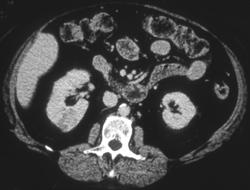

Oncocytoma